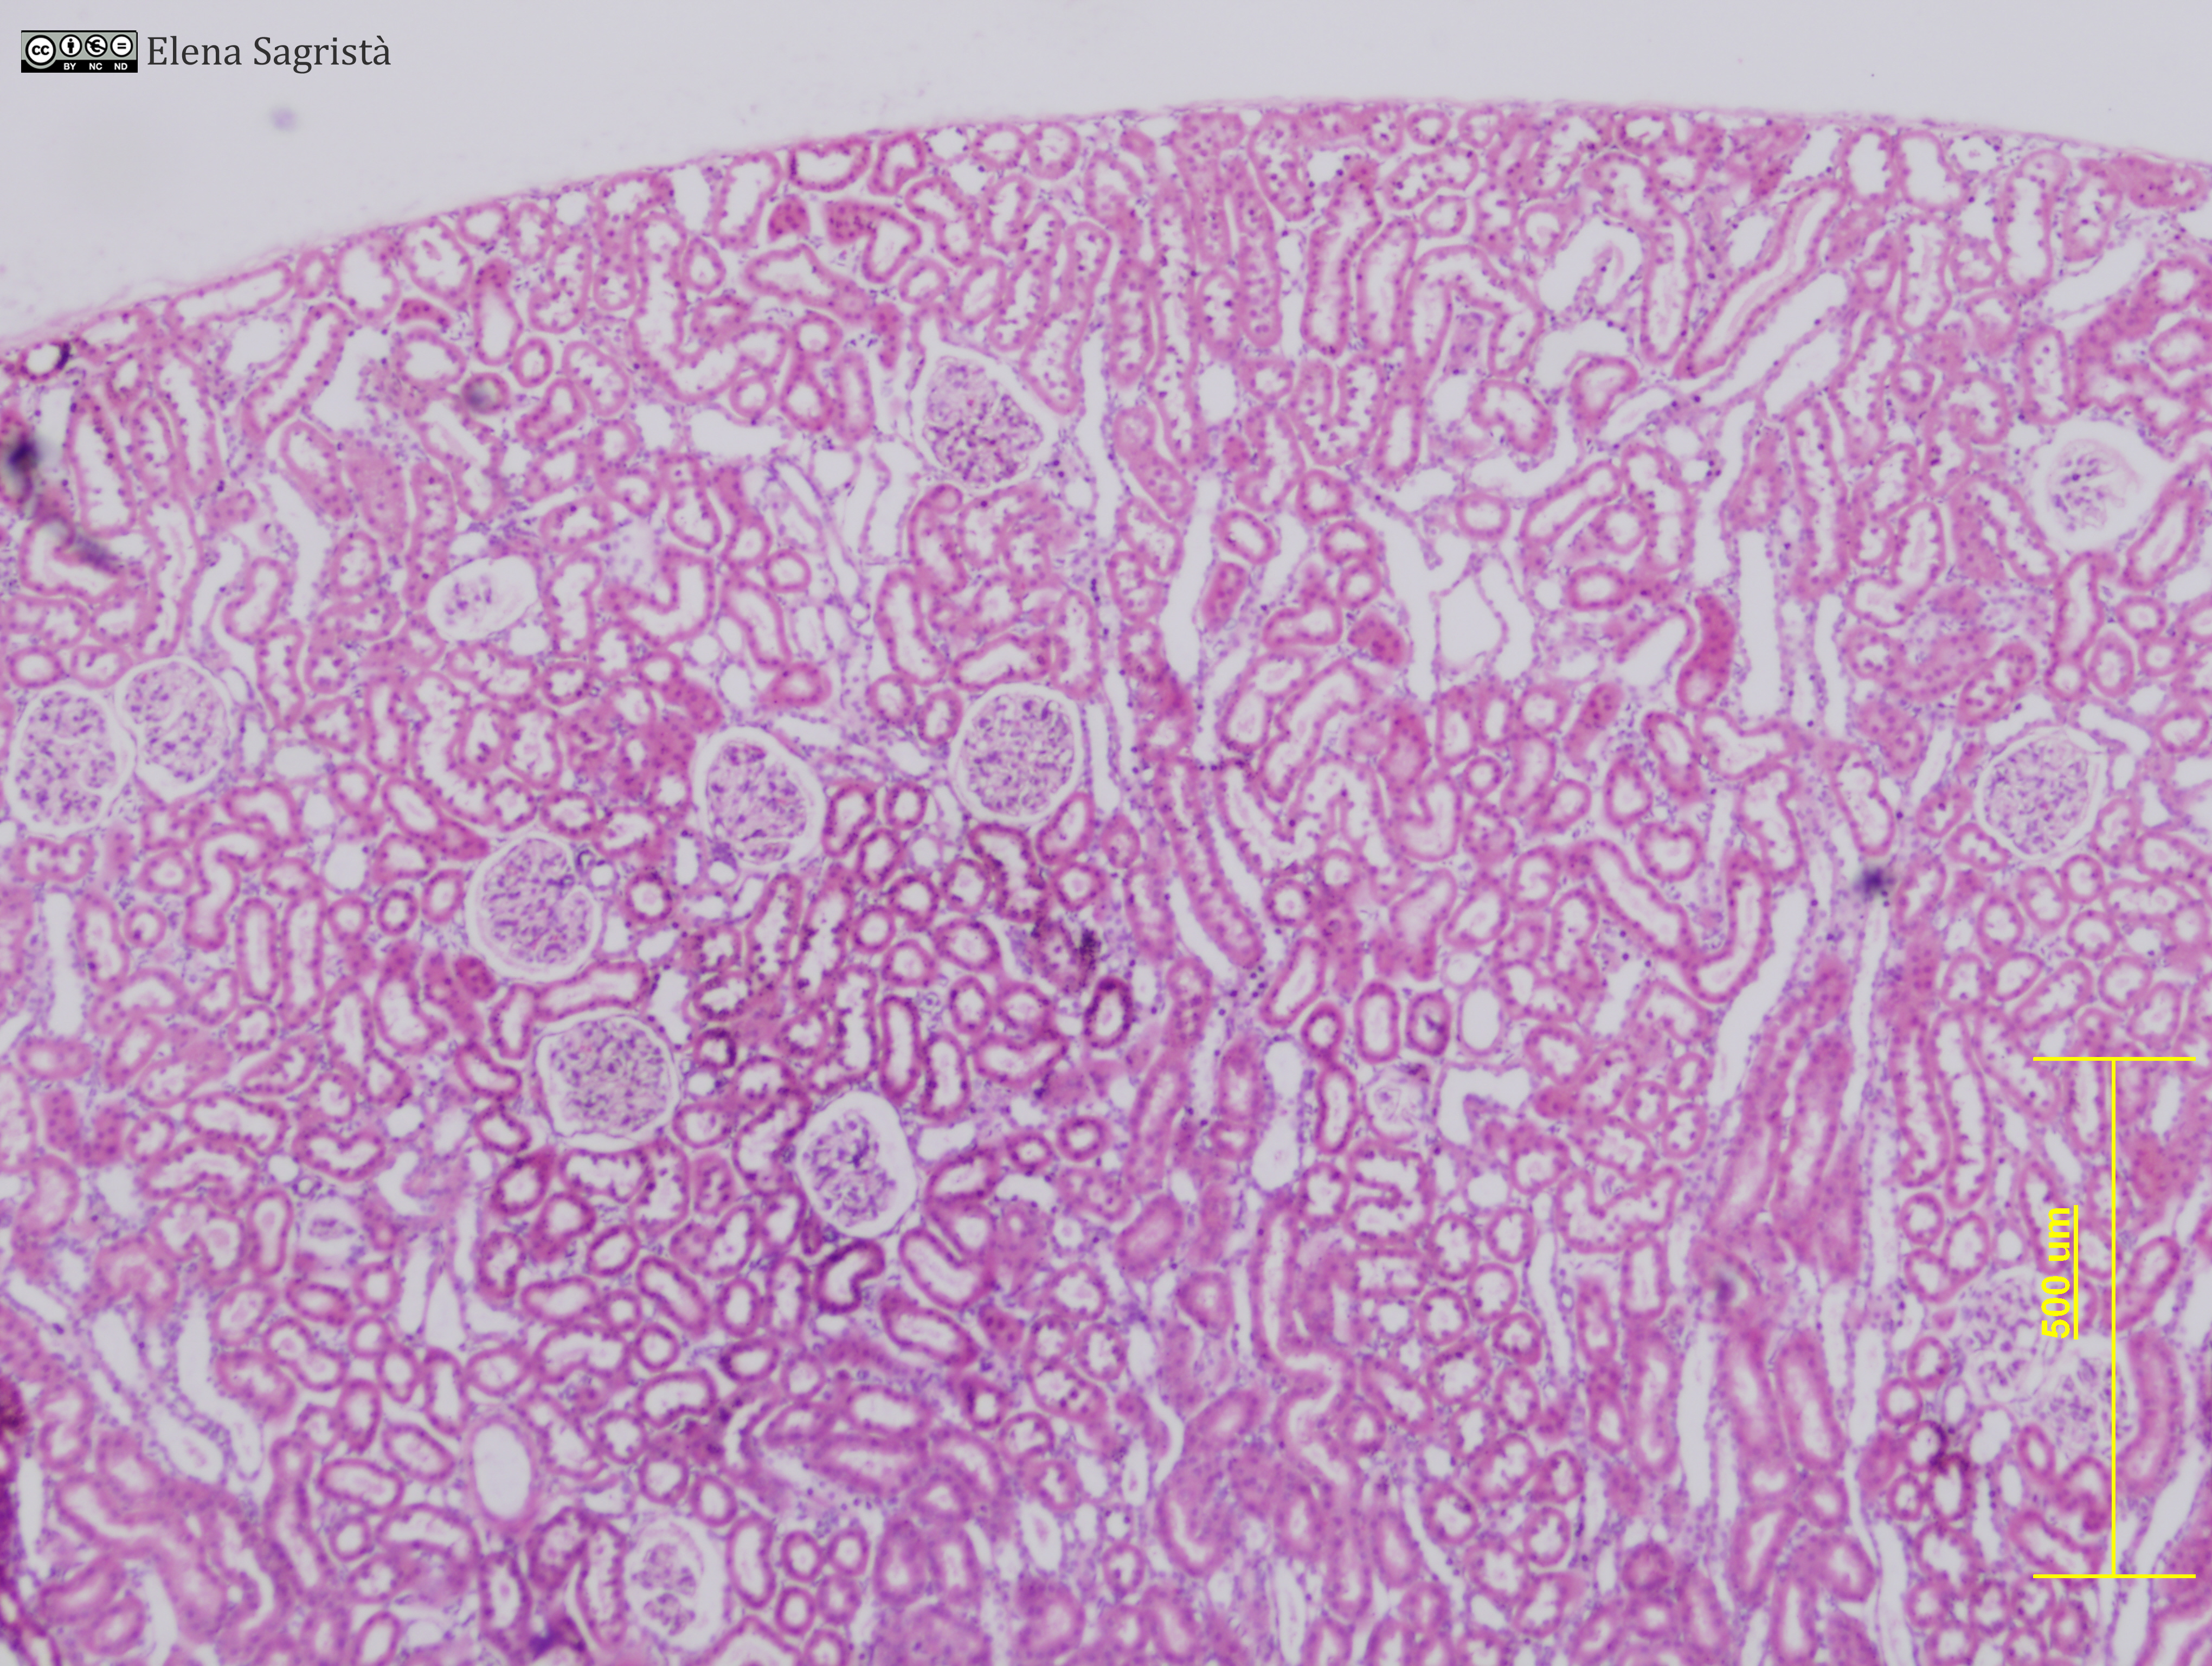

Histologia imatges: 21 Ronyò i Bufeta

Imatges de preparacions histològiques de Ronyò i Bufeta. Microscopia òptica.